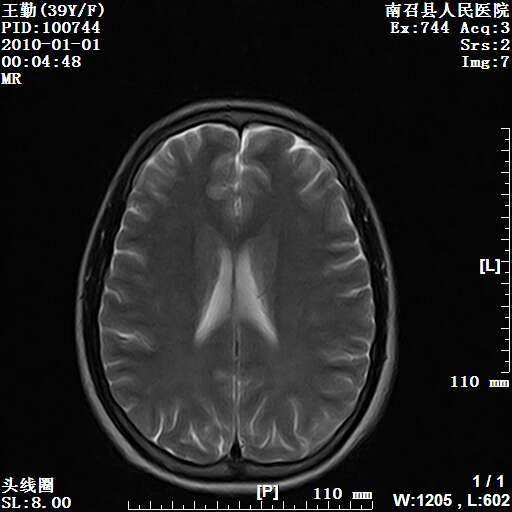

以下是引用随光逐影在2010-1-22 9:03:00的发言:[br]考虑左侧中颅窝(蝶骨翼区)脑膜瘤侵犯蝶骨翼并突入左侧眼眶。

以下是引用水过无痕在2010-1-22 14:55:00的发言:[br]一、定位:颅外占位;二、定性:恶性可能性大;三、组织来源:来源于左侧眼外直肌或其他部位;考虑为:横纹肌肉瘤>转移瘤>脑膜瘤.